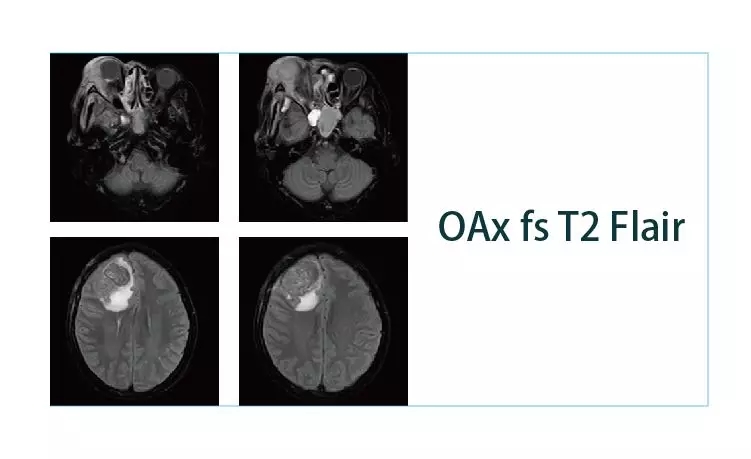

【朗润影像档案】20190118磁共振影像病例结果讨论